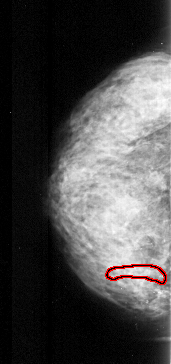

A_1000_1.LEFT_MLO

LEFT_MLO LINES 4861 PIXELS_PER_LINE 2521 BITS_PER_PIXEL 16 RESOLUTION 42 OVERLAY

FILE: A_1000_1.LEFT_MLO.OVERLAY

TOTAL_ABNORMALITIES 1

ABNORMALITY 1

LESION_TYPE CALCIFICATION TYPE PLEOMORPHIC DISTRIBUTION CLUSTERED

ASSESSMENT 4

SUBTLETY 2

PATHOLOGY MALIGNANT

TOTAL_OUTLINES 1

BOUNDARY